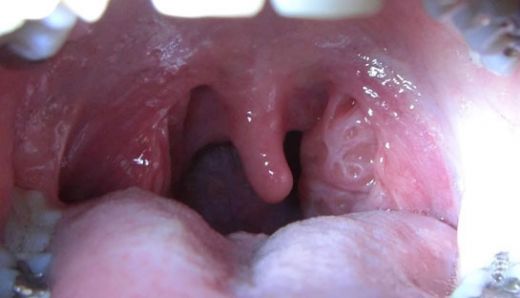

Sol bademciğinizin şişmesi ve yutkunma zorluğu yaşamanız, genellikle bademcik iltihabı ile ilişkilendirilebilir. Bademciklerin iltihaplanması, çevresindeki dokulara da etki edebileceği için kulak ağrısı gibi belirtiler ortaya çıkabilir. Bu durum, bademciklerin ve çevresindeki lenf dokularının iltihaplanması sonucu gelişir.

Sol bademcik şişmesi yaşadım ve gerçekten rahatsız edici bir durum. Boğazımda ağrı ve yutkunma güçlüğü ile birlikte beyaz lekeler oluştu. Tedavi için doktora başvurdum. Tek taraflı bademcik şişmesi doktor sitesinde de belirttiği gibi önemli bir durum, dikkat edilmesi lazım.

Alpartur, yaşadığın bu durum gerçekten de rahatsız edici olabilir. Boğazdaki ağrı ve yutkunma güçlüğü, günlük yaşamı olumsuz etkileyebilir. Beyaz lekelerin varlığı, enfeksiyon belirtilerine işaret edebilir ve bu nedenle doktora başvurman çok önemli bir adım.

Dikkat Edilmesi Gerekenler

Tek taraflı bademcik şişmesi, bazen daha ciddi durumların bir belirtisi olabileceğinden, doktorun önerilerini dikkatle takip etmekte fayda var. Özellikle ateş, şiddetli ağrı veya nefes alma zorluğu gibi belirtiler varsa, derhal sağlık kuruluşuna başvurmak gerekebilir.